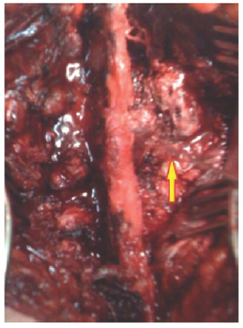

The embolization of the aneurysm has been excluded from the management plane, because the spinal cord needed urgent surgical decompression. The patient sent to the OR for urgent spinal cord decompression surgery, complete T10 laminectomy with excision of the mass in the right lamina pedicle and T9-T10 facet joint was performed. Segmental T9-T10 fixation and fusion was done as showen in (Figure 8 & 9)

Figure 8:

Figure 9: